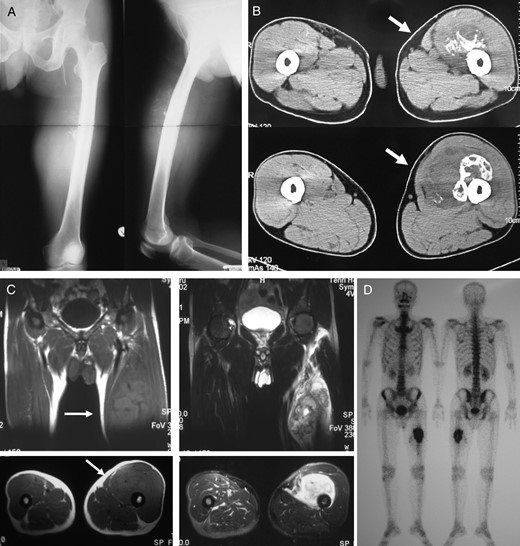

Case 1: A 61-year-old male was treated at the age of 54 for primary soft-tissue sarcoma of the thigh which invaded the femur (Fig. 1A–D). Wide en bloc resection of the tumor with involved femoral diaphysis, isolation of the tumor with involved bone, extracorporeal irradiation with 50 Gy as a single bolus dose to the isolated bone and reimplantation of the irradiated bone into the host with intramedullary nail were performed (Fig. 2A). At 74 months after primary surgery, graft bone fracture and intramedullary nail breakage occurred at the proximal diaphysis (Fig. 2B). Segmental intercalary resection, implant removal and reconstruction with custom-made intercalary prosthesis were performed (Fig. 2C and D). The best MSTS score was 20 of 30.

A 54-year-old male with primary soft tissue sarcoma. Plain radiograph (A) and CT (B) showing lytic destructive lesion in left femoral diaphyseal bone. T1- and T2-weighted magnetic resonance imaging (C) showing a soft tissue mass (20 × 20 × 12 cm) around femoral bone. Bone scintigraphy (D) showing increased uptake in femoral diaphyseal bone.